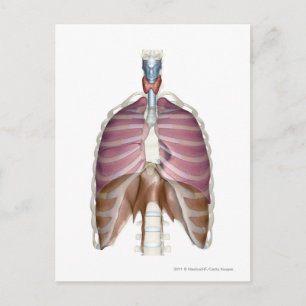

Hjärtans och lungornas struktur poster

Pris343,00 kr